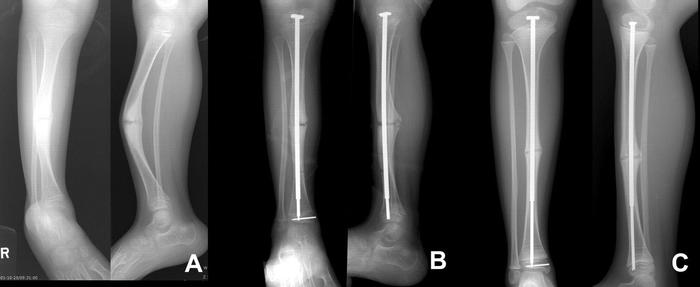

Применяются и хирургические ортопедические методы, например, остеосинтез при помощи телескопических штифтов, вводимых вовнутрь кости в детстве и «растущих» вместе с ней. Физиотерапия, которая сводится к улучшению мышечного каркаса, а также совершенствованию координации, что позволяет избегать падений, а значит и переломов. Хороший эффект показывает гидротерапия, особенно для ускорения заживления уже существующих переломов. Пациенты принимают витамин Д3 и препараты кальция.

Остеосинтез при помощи телескопических штифтов:

С хирургической стороны давно назрела идея, что для механического укрепления "хрустальных" костей нужно вставлять в них металлические стержни. Проблем было несколько. Первая - оперировать нужно до того, как ребёнок вырастет, а следовательно, имплантируемая конструкция (словосочетание-то какое красивое!) должна "расти" вместе с дитём. Ну, тут решение простое. Всем известны телескопические конструкции на манер раздвижной антенны приёмника. Проблема вторая состоит в том, что для восстановления правильной ориентации ноги или руки во время установки конструкции в кость, ранее сломанную далеко не один раз, приходится снова ломать, часто в нескольких местах, и собирать в правильном положении, буквально нанизывая по частям на металлический стержень. Сравнение, произнесённое дружбаном, я не стану здесь приводить, сами знаете, какие у медиков шуточки бывают циничные! Так вот, на этом этапе возникает другая проблема: части костей не должны вращаться после операции, т.е. должны быть "ротационно стабильными". И вот эта-то проблема и была решена харьковскими врачами. Решение оказалось вполне простым и на сегодняшний день по этой методике пролечен уже не один десяток пациентов. Понятное дело, что всех тонкостей лечения я не расскажу в силу отсутствия профильного образования, а фотками своих пациентов друг не поделится по этическим соображениям.